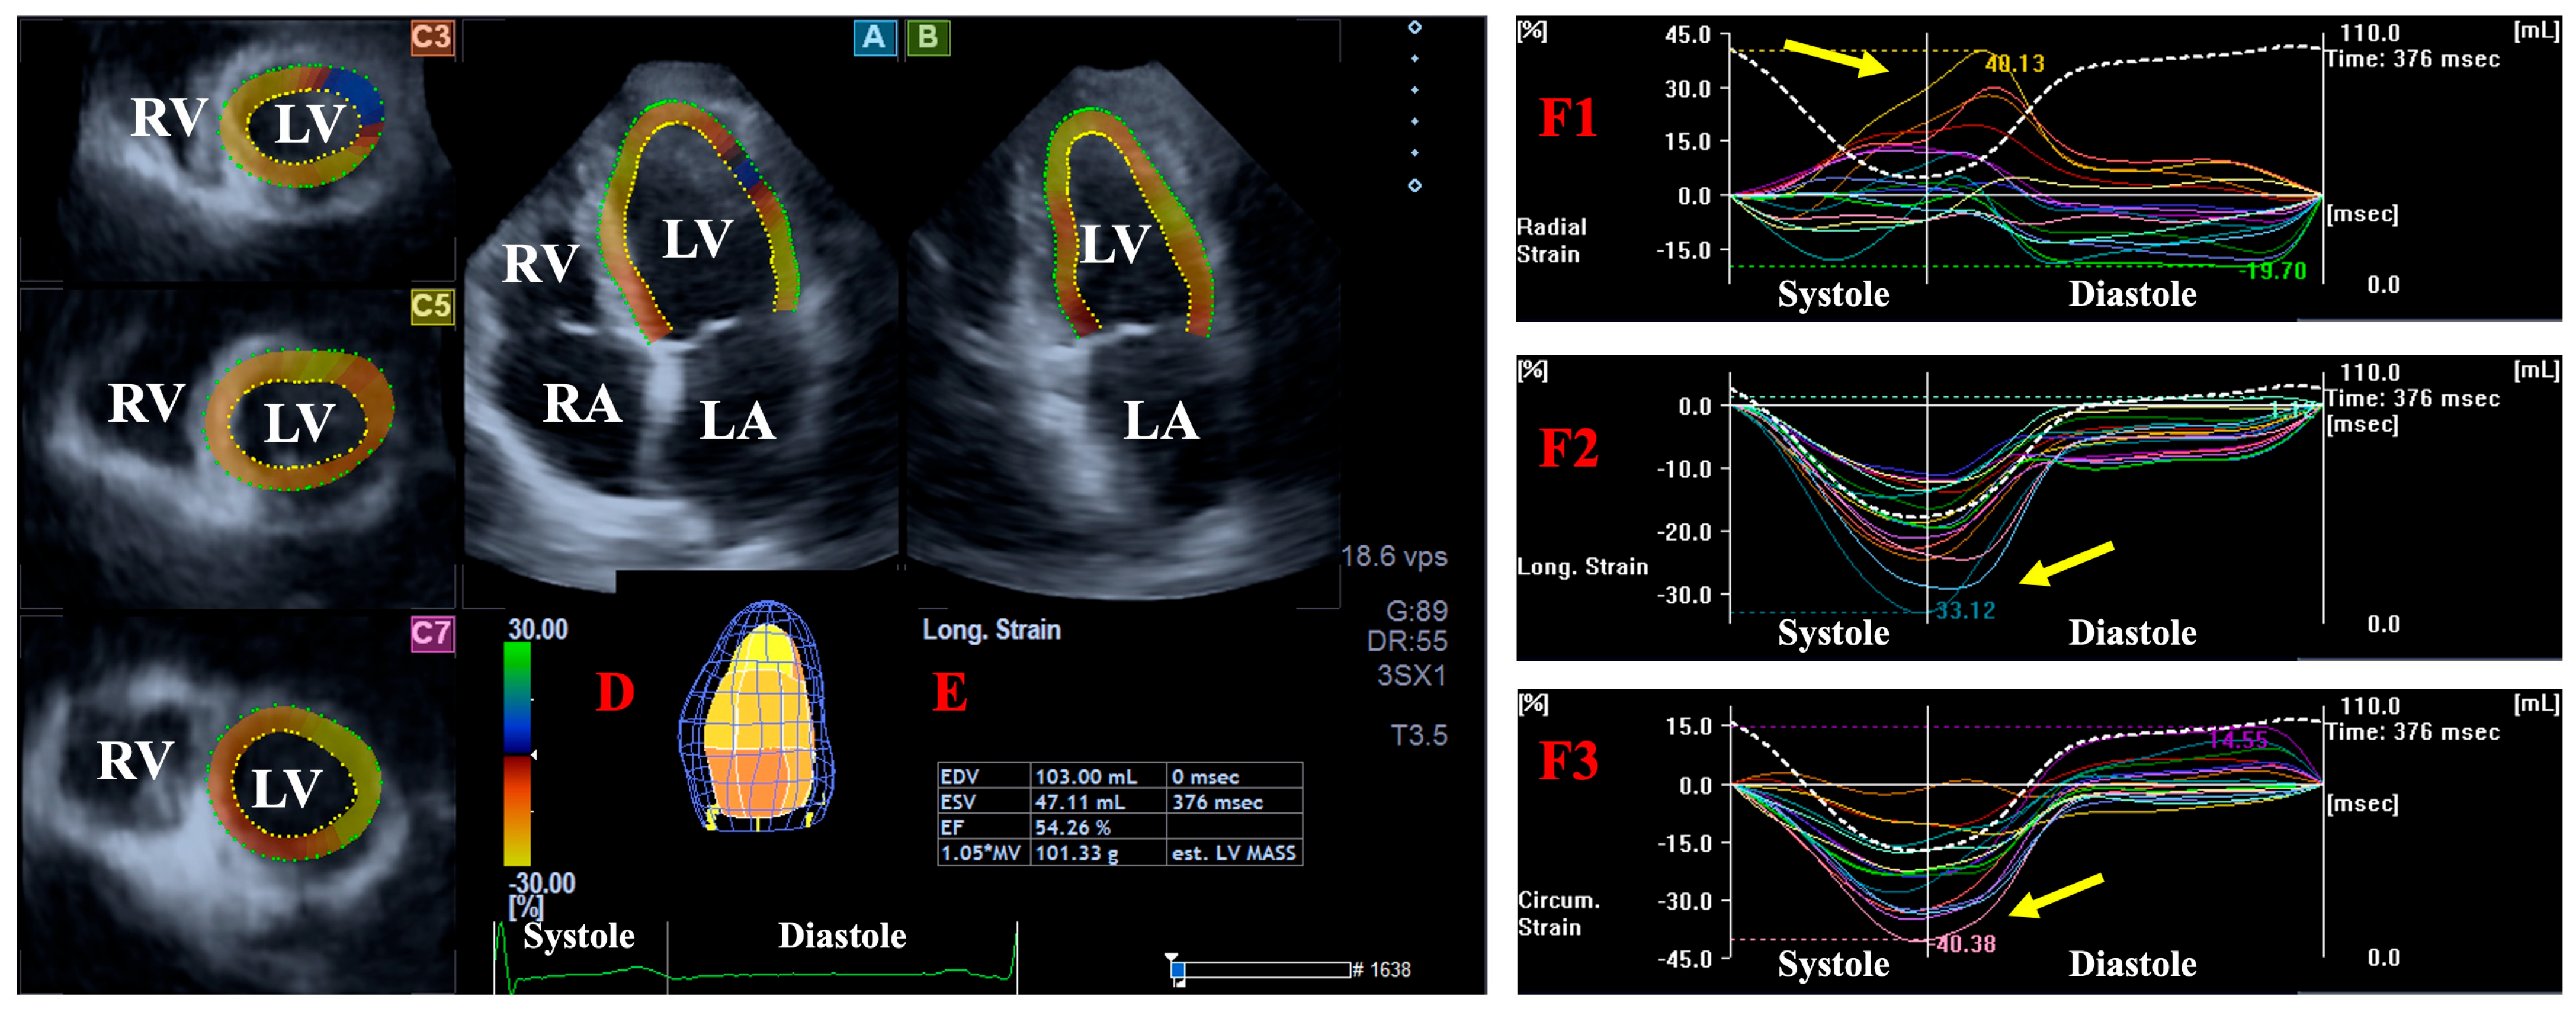

2.4. DSTE-Derived LA/LV Volumes and Strains

- LA/LV radial strain (LA/LV-RS), featuring the thinning/thickening of the myocardial tissue.

- LA/LV circumferential strain (LA/LV-CS), featuring the widening/narrowing of the myocardial tissue.

- LA/LV longitudinal strain (LA/LV-LS), featuring the lengthening/shortening of the myocardial tissue.